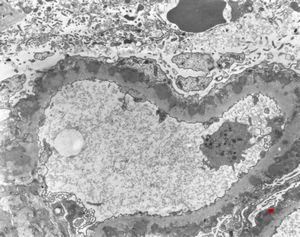

F,14y. | Alport syndrome - split and laminated, thick/thin basement membranes